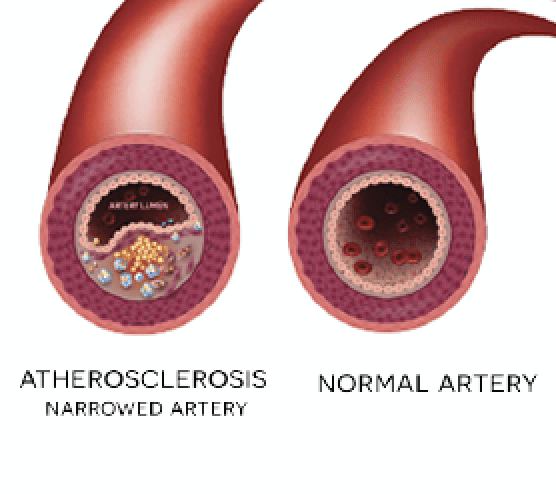

Peripheral Arterial Disease

Peripheral Artery Disease (PAD) is a medical condition characterized by narrowing of the arteries in the legs, causing a reduction in circulation to  the toes, feet and legs. This can occur as a result of smoking, high cholesterol, diabetes or high blood pressure. The arteries can narrow or completely be blocked reducing the blood supply to the legs. The cramping symptoms are worse on exercising because the narrowed arteries cannot meet the muscles demand for oxygen. Left untreated, PAD can lead to amputation and put you or your loved one’s quality of life and long-term health at serious risk.

the toes, feet and legs. This can occur as a result of smoking, high cholesterol, diabetes or high blood pressure. The arteries can narrow or completely be blocked reducing the blood supply to the legs. The cramping symptoms are worse on exercising because the narrowed arteries cannot meet the muscles demand for oxygen. Left untreated, PAD can lead to amputation and put you or your loved one’s quality of life and long-term health at serious risk.